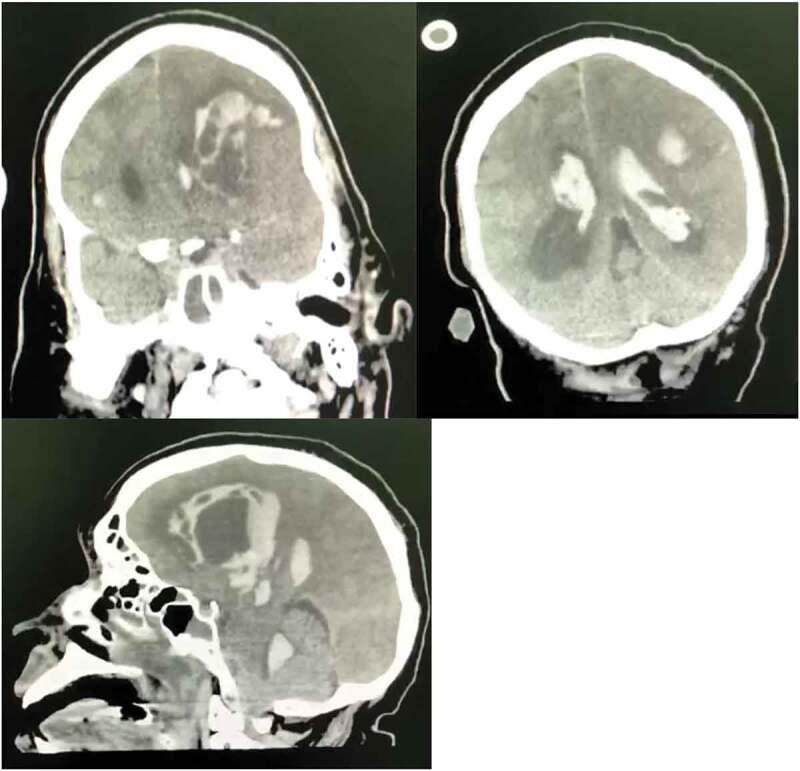

There is growing evidence in support of ischemic stroke as a manifestation of COVID-19 infection. However, hemorrhagic transformation of ischemic stroke is rare. We present two cases of hemorrhagic infarction as presenting features in COVID-19 patients who did not have traditional cardiovascular risk factors for ischemic or hemorrhagic stroke. While the hemorrhagic infarct was from a large artery in one of the patients, the other patient had a small artery related hemorrhagic infarct. We highlighted the possible underlining mechanisms from the literature and the implication of hemorrhagic infarct for routine anticoagulant therapy in patients with COVID -19 related ischemic stroke.

越来越多的证据支持缺血性中风是新冠病毒感染的一种表现。然而,缺血性中风的出血性转化很少见。我们报告了两例以出血性梗死为首发特征的新冠病毒感染患者,他们没有缺血性或出血性中风的传统心血管危险因素。其中一例患者的出血性梗死源于大动脉,另一例患者的出血性梗死与小动脉有关。我们从文献中强调了可能的潜在机制以及出血性梗死对新冠病毒相关缺血性中风患者常规抗凝治疗的影响。